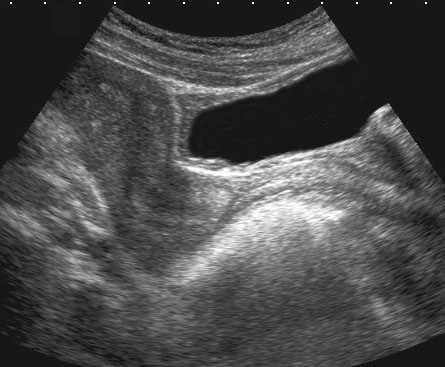

Trên mặt phẳng đứng dọc có thể xác định được tử cung, cổ tử cung, âm đạo, trực tràng hậu môn và niệu đạo (u.), cũng như túi cùng trước và túi cùng sau của âm đạo ở trạng thái xẹp.

Nghiên cứu tử cung ở tư thế gập sau đòi hỏi bàng quang phải được làm đầy nhiều hơn.